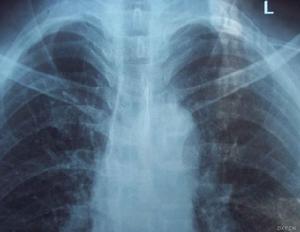

(2)縱隔炎和膿腫:一般是尖銳異物刺入過深而繼發感染。頸部異物可在頸深部形成蜂窩組織炎和膿腫,炎症還可由此向下擴散至上縱隔,並發展為縱隔炎和膿腫。食管胸段穿孔更必然發展成為縱隔炎和膿腫。縱隔炎和膿腫的臨床症狀為胸骨後劇烈疼痛、高熱及全身中毒症狀,甚至出現中毒性休克。X線影像學檢查可見縱隔明顯增寬,胸骨後密度增加,部分患者可見到膿腫液平面及液氣胸等。對顯影不佳者,可行CT掃描以顯示病變部位。縱隔膿腫的病死率可高達30%~55%,對嵌頓於胸段食管主動脈弓和支氣管分權處的異物應高度警惕,防止發生此併發症。

此類併發症多由食管內滯留液體或食物殘渣反流吸入氣管內,引起的一系列症狀。最常見的有支氣管炎、肺不張、吸入性肺炎及肺膿腫等。患者可出現嗆咳、發熱、呼吸困難等症狀,物理檢查則發現肺部囉音、肺小葉實變等。X線拍片則發現肺部紋理增粗、片狀模糊影或肺葉不張等影像學徵象。